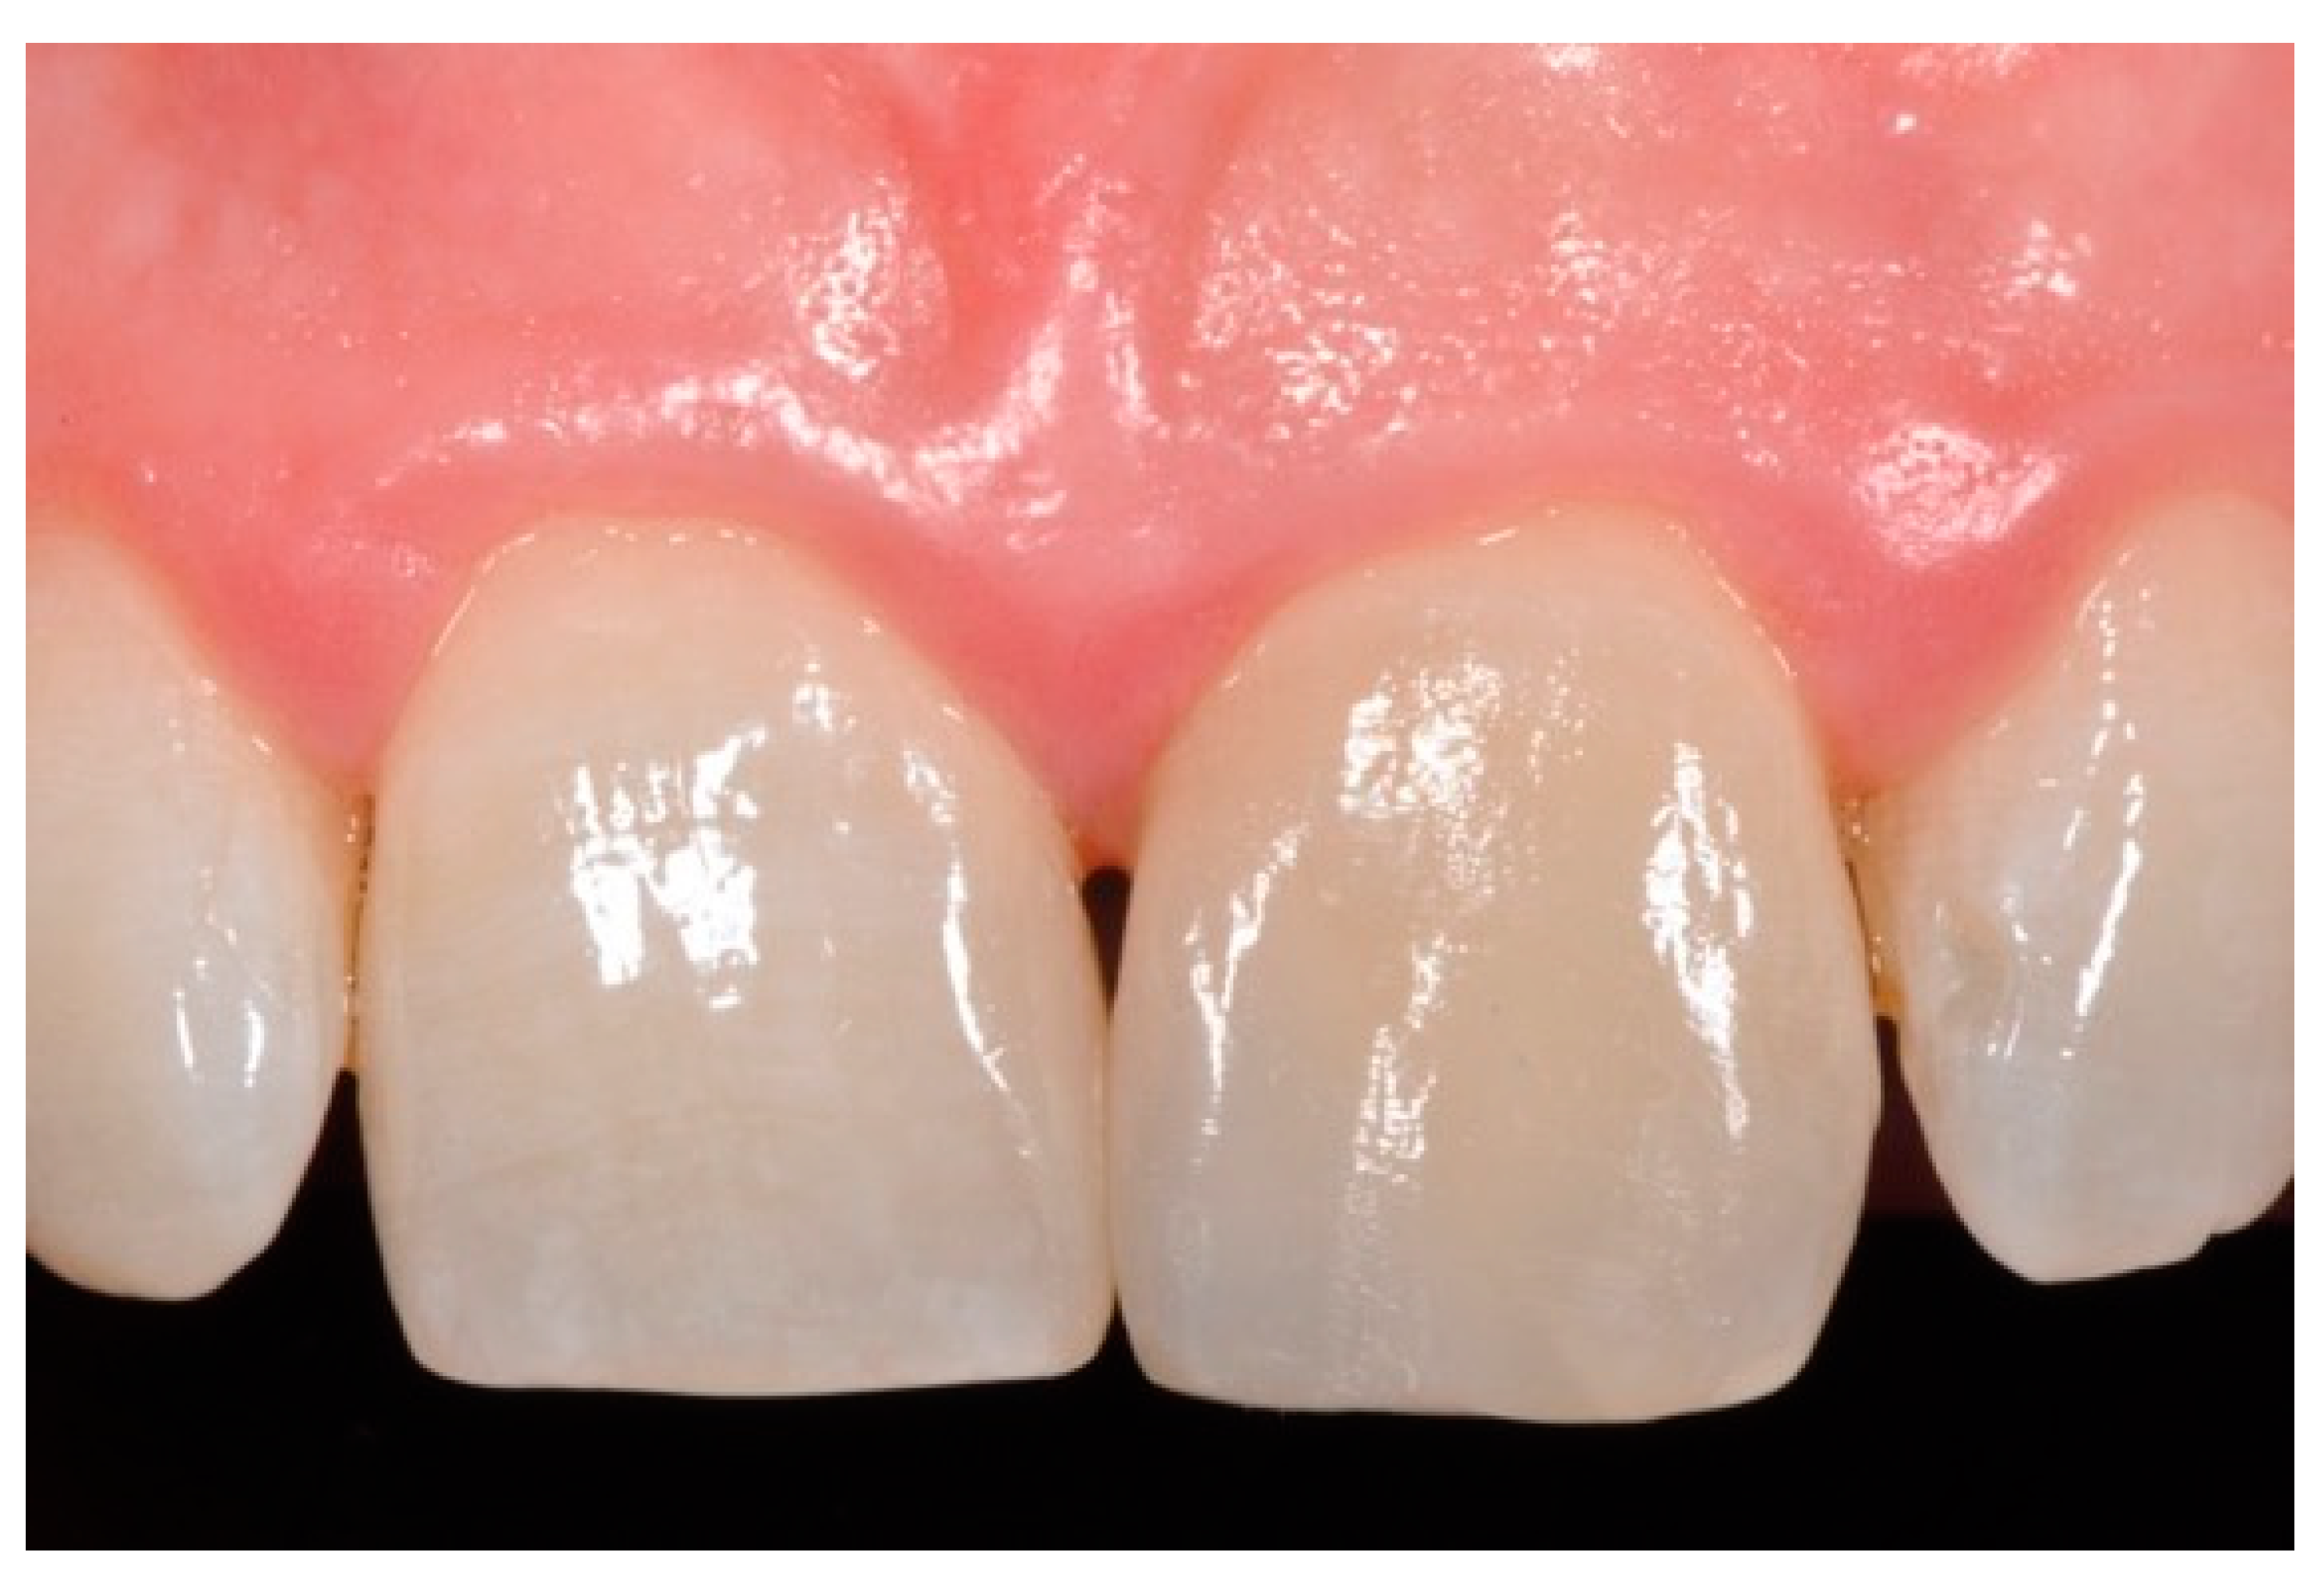

Figure 15.

Three months post-operative. Reprinted from Restauri diretti nei settori anteriori, G. Paolone, S. Scolavino, © 2021, with permission from Quintessence Publishing Italy.

Figure 16.

One year post-operative. Reprinted from Restauri diretti nei settori anteriori, G. Paolone, S. Scolavino, © 2021, with permission from Quintessence Publishing Italy.